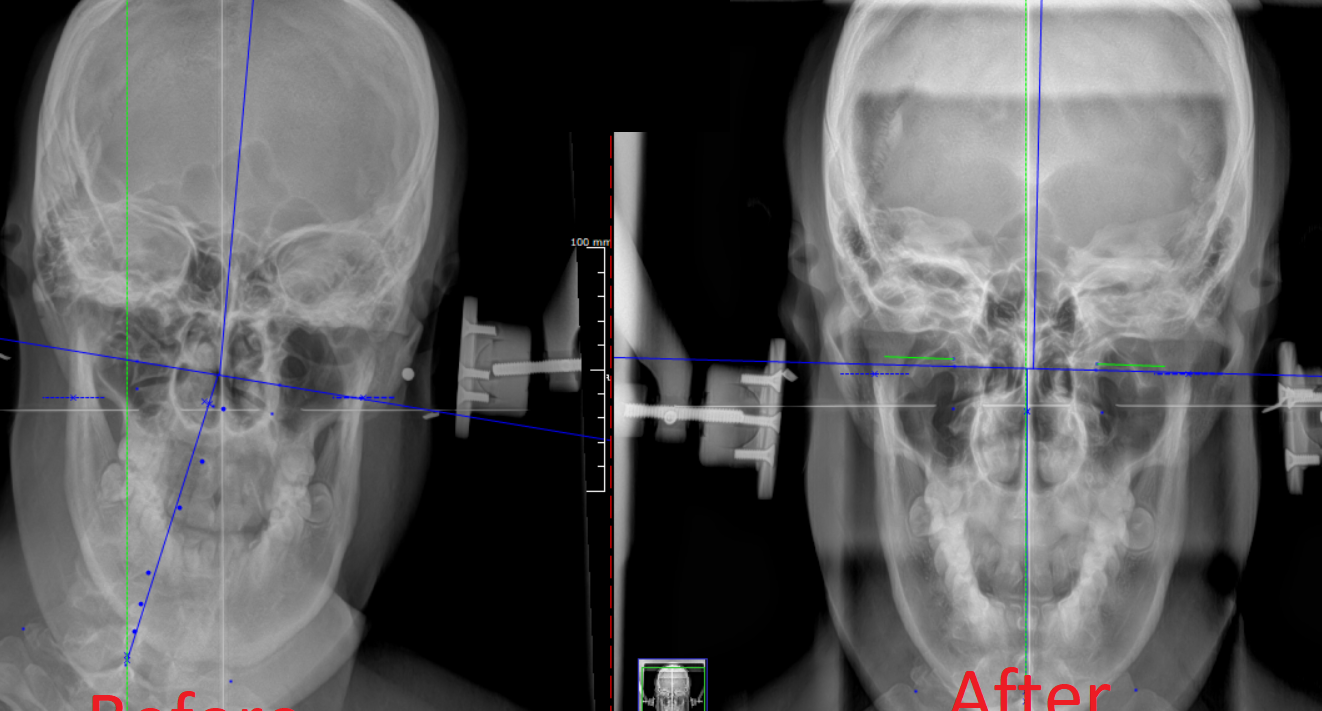

Pelarasan Tulang oleh Muqlas adalah rawatan chiropractic yang dilakukan oleh Muqlas, seorang chiropractor yang berpengalaman di Malaysia. Rawatan ini bertujuan untuk mengembalikan keseimbangan dan menghilangkan kesakitan pada tulang belakang dan sendi.

Pelarasan Tulang oleh Muqlas mempunyai beberapa kelebihan, termasuk mengurangkan kesakitan, meningkatkan mobiliti, dan mengembalikan keseimbangan pada tulang belakang dan sendi. Rawatan ini juga dapat membantu mengurangkan tekanan dan meningkatkan kesihatan secara keseluruhan.